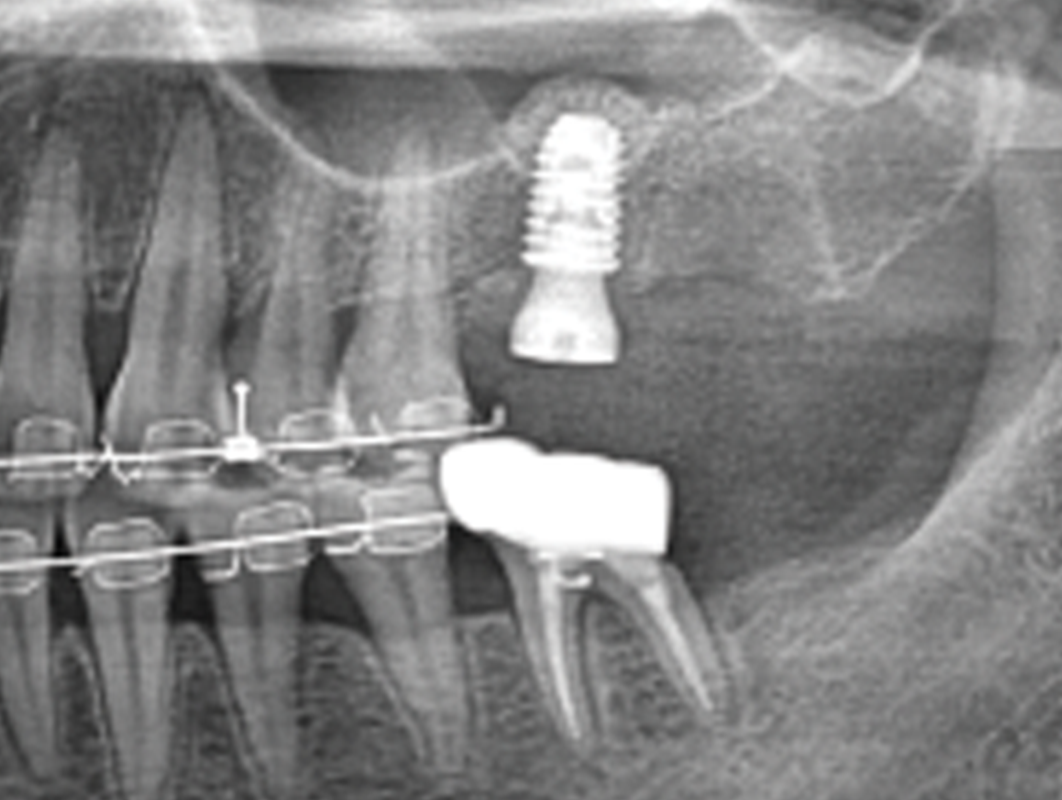

02

PRE-RACE DIAGNOSTICS – PREOPERATIVE ASSESSMENT

Radiographic and Clinical Evaluation – Scouting the Route

Just like drivers need a map of the race track, surgeons need a clear view of the sinus structure. We’ll cover CBCT analysis and key anatomical landmarks to keep you in the race

02

PRE-RACE DIAGNOSTICS – PREOPERATIVE ASSESSMENT

Radiographic and Clinical Evaluation – Scouting the Route

Just like drivers need a map of the race track, surgeons need a clear view of the sinus structure. We’ll cover CBCT analysis and key anatomical landmarks to keep you in the race

Sinus Floor Elevation with Implant Placement – Timing is Everything

Like perfectly timed gear shifts, the sequence of sinus lifts and implant placements is key. We’ll cover when to “accelerate” and when to hold back for best outcomes.

Sinus Floor Elevation with Implant Placement – Timing is Everything

Like perfectly timed gear shifts, the sequence of sinus lifts and implant placements is key. We’ll cover when to “accelerate” and when to hold back for best outcomes.